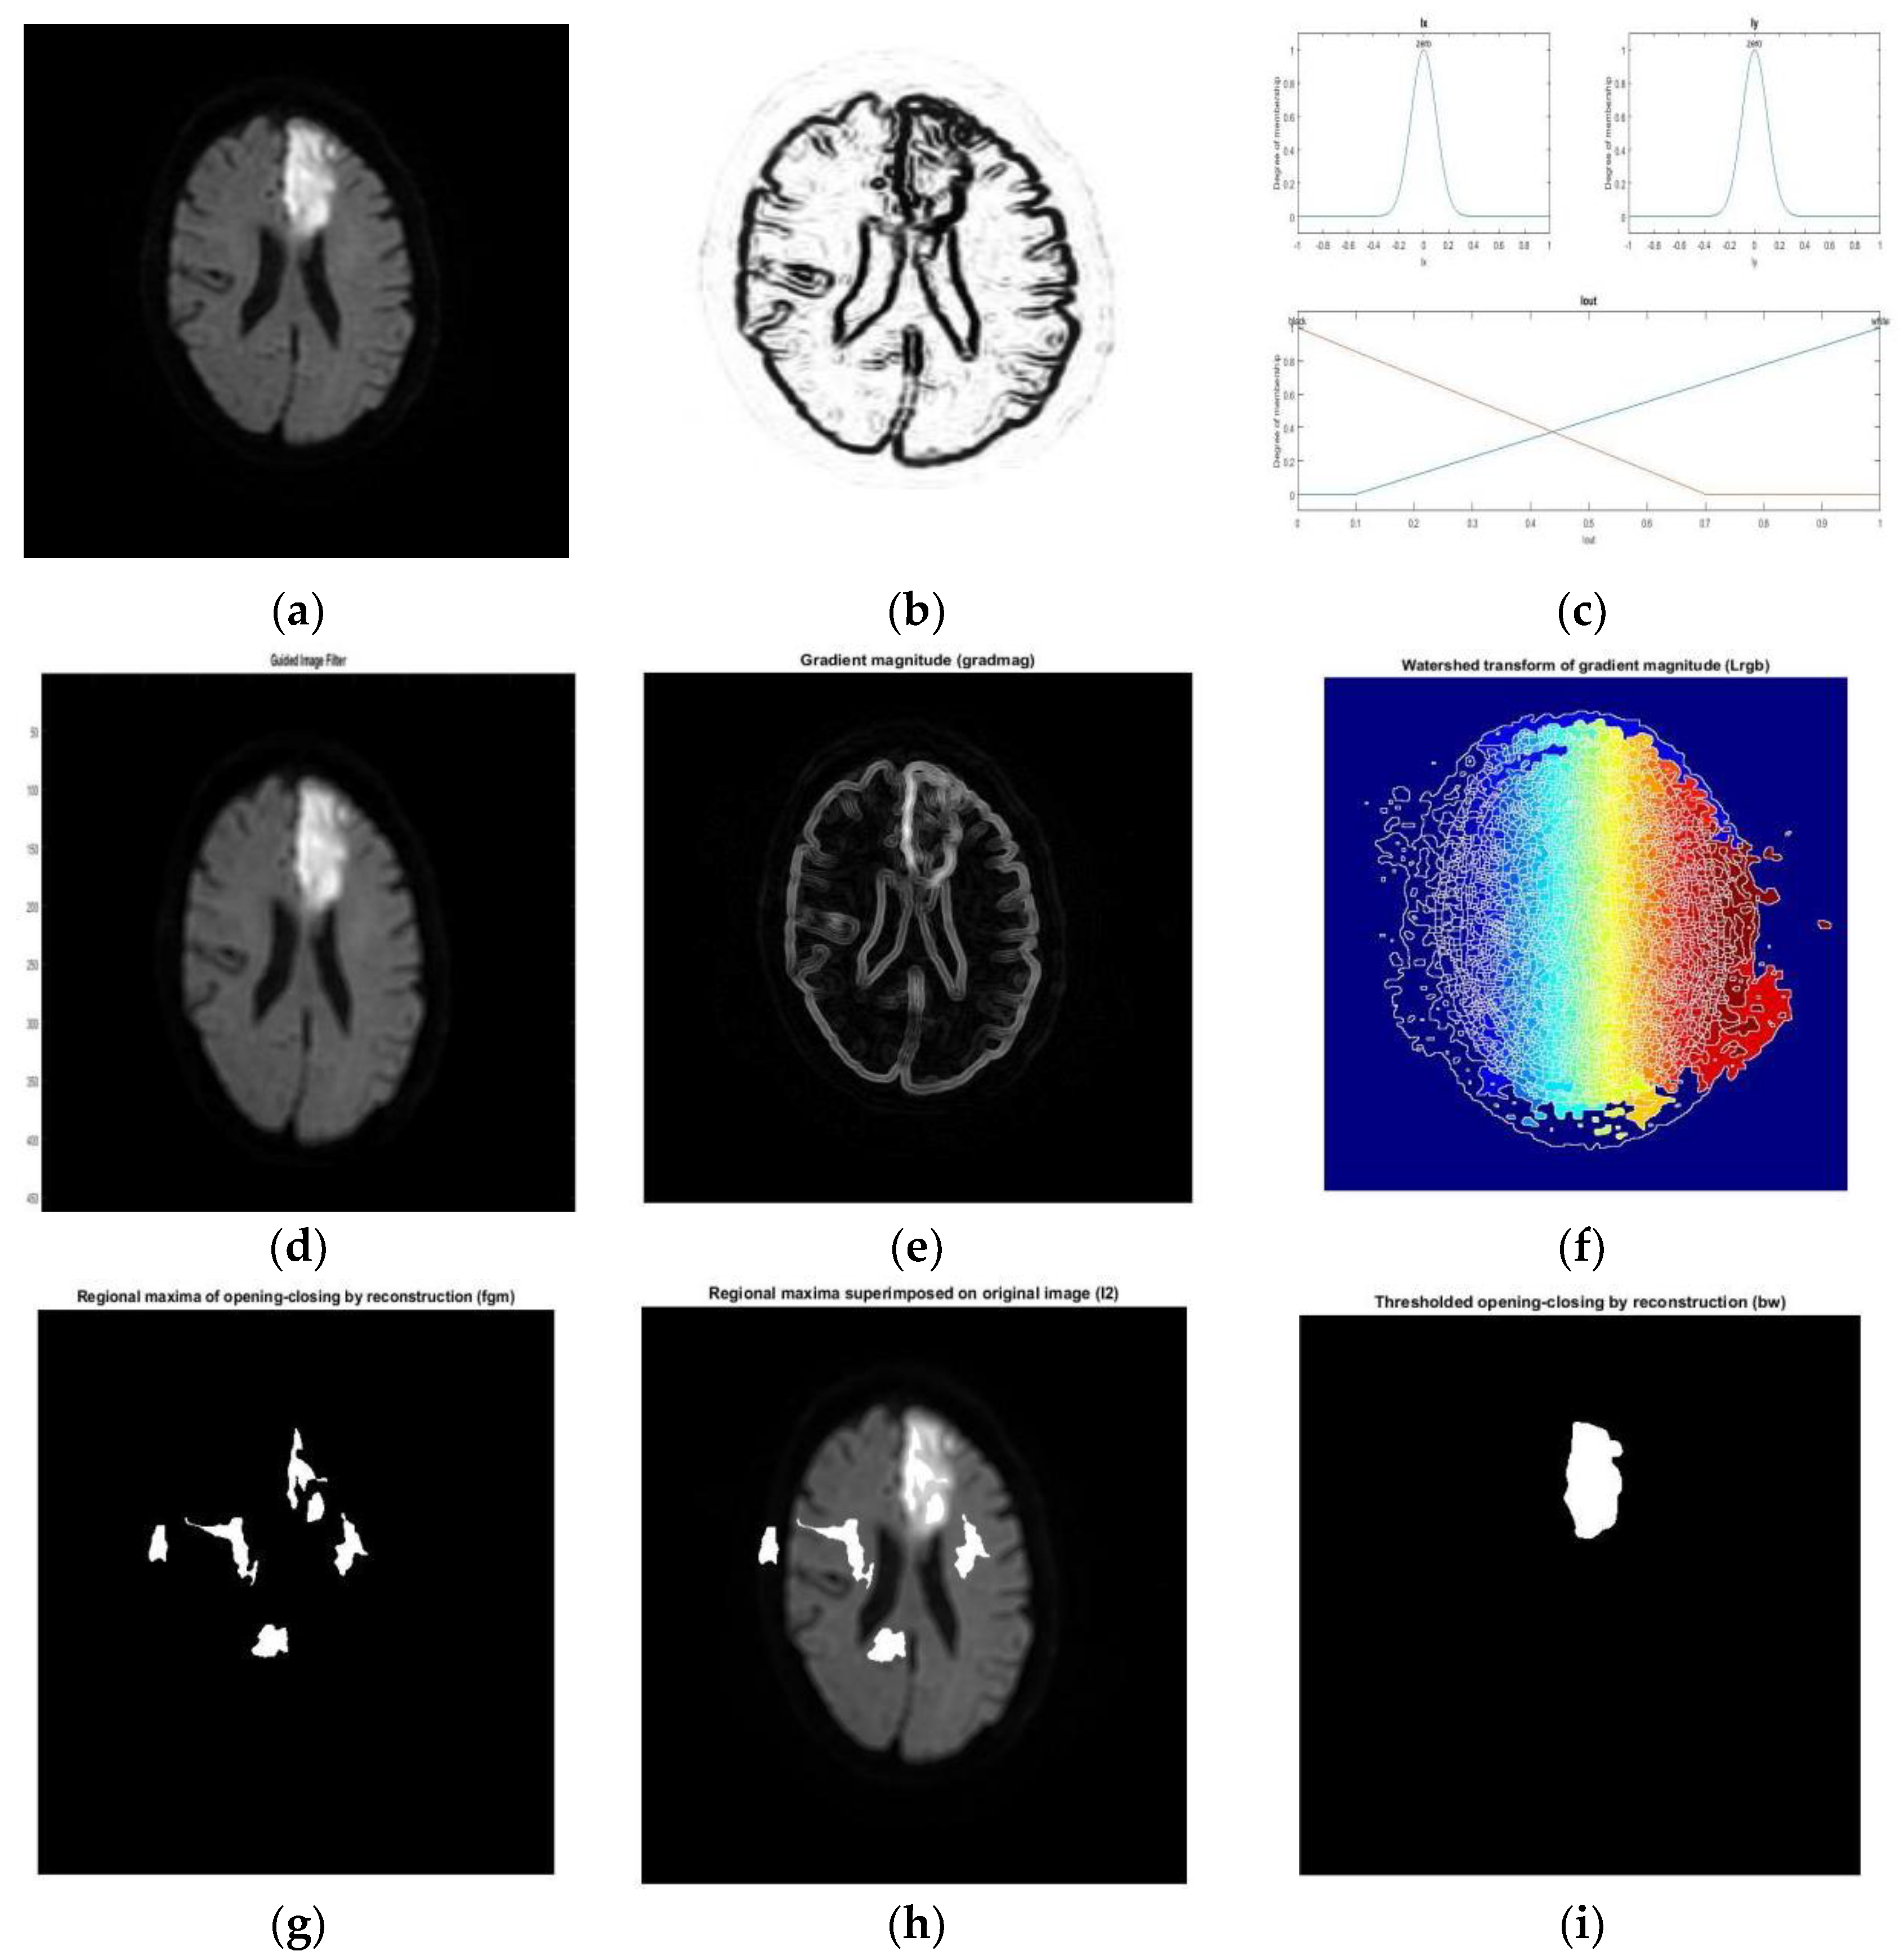

- Subudhi, A.; Jena, S.; Sabut, S. Delineation of the ischemic stroke lesion based on watershed and relative fuzzy connectedness in brain MRI. Med Biol Eng Comput. 2018, 56, 795–807. [Google Scholar] [CrossRef]